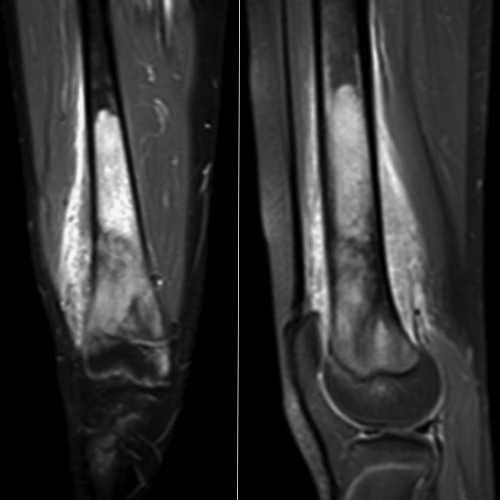

سارکوما الأنسجه الرخوه هی مجموعه من السرطانات النادره التی تؤثر على الأنسجه التی تربط وتدعم وتحیط بهیاکل وأعضاء الجسم الأخرى.

فی الواقع، تتشکل الأورام اللحمیه من الأنسجه الضامه مثل الغضاریف والعضلات والعظام، ولهذا السبب، غالبًا ما تسمى السرطانات التی تتطور فی العظام والعضلات بالسارکوما.

لأن الأورام اللحمیه تصیب الأنسجه الرخوه مثل العضلات أو العظام أو المفاصل وتسبب مشاکل خطیره للفرد، ولهذا الغرض یجب استشاره أخصائی العظام لعلاجها.

من المهم أن نعرف أن سارکوما الأنسجه الرخوه یمکن أن تحدث فی أی جزء من الجسم تقریبًا، بما فی ذلک الساقین والذراعین والبطن.